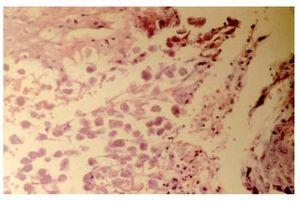

Con la finalidad de descartar la presencia de un carcinoma epidermoide anal, se realizó biopsia de la lesión exofítica y el estudio histopatológico reportó amibiasis cutánea (Figura 2). El paciente fue tratado con metronidazol 500 mg vía oral cada ocho horas durante 10 días y baños de asiento en agua tibia tres veces al día, observándose remisión de las lesiones, después de tres semanas.

¿ Figura 2. Microfotografía a mediano aumento, con hematoxilina y eosina, en donde observan trofozoítos de Entamoeba histolytica en una úlcera cutánea perianal.